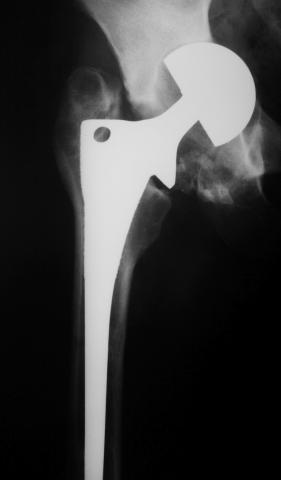

Уважаемые коллеги! молодой человек 22 лет обратился к нам с жалобами на умеренную боль в в/3 левого бедра и паху при ходьбе, укорочение левой ноги. 3 года назад получил закрытый перелом шейки левого бедра (рис 1).

Лечился в стержневом аппарате по месту жительства. АВФ демонтировали через полгода из-за воспаления в области стержней (рис 2). После демонтажа в течение месяца больной лихорадил до 38*, были боли в бедре. Эти явления исчезли после курса антибиотиков. Через год после травмы в ЦРБ ему имплантировали биполярный протез (рис 3). Рана зажила первично. Ходил с костылями, слегка приступая на ногу. На контрольных осмотрах выявлена прогрессирующая протрузия (рис 4-6).